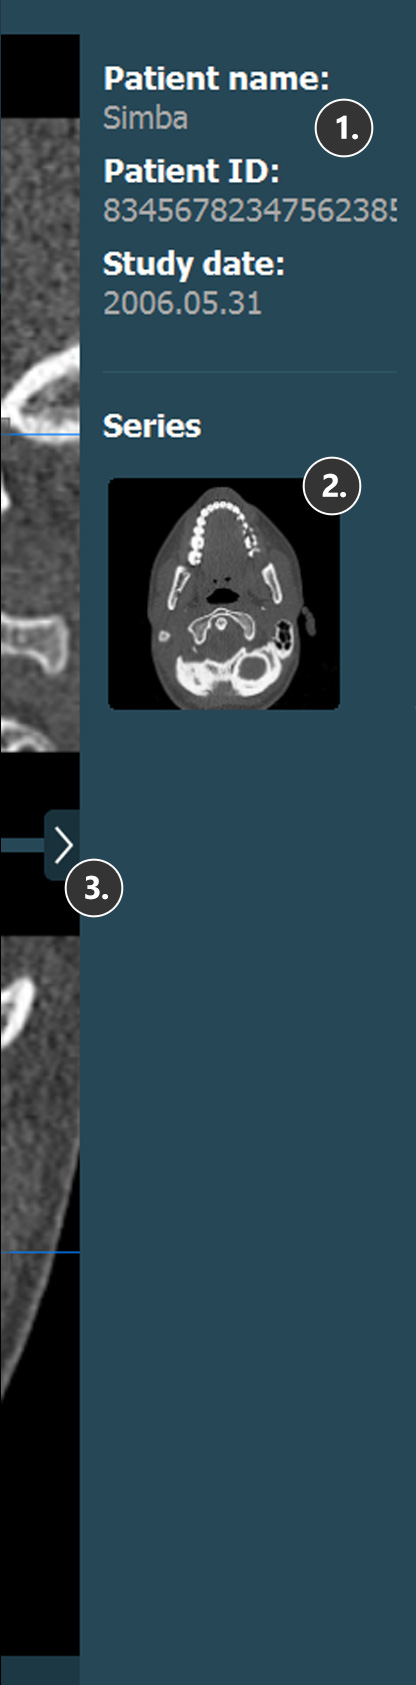

Patient information

Study information